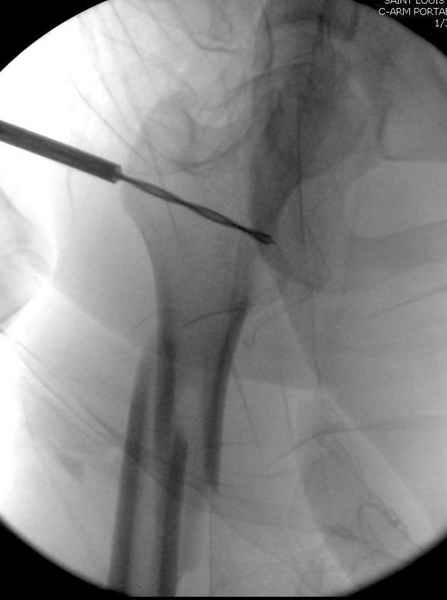

Второй случай тоже репозиция из малого доступа, больному 19 лет, множественные огнестрельные повреждениия конечностей, живота и черепа, правая конечность холодная, без пульсации. Ортопедический диагноз: огнестрельный перелом правого бедра. При срочной ангиографии повреждения сосудов не подтвердилось, конечность из-за ургентности состояния больного зафиксирована временным наружным фиксатором и больной оставлен на операционном столе для срочной лапаротомии хирургической службой.

Больной долго оставался нестабильным, только на 14 день удалось заменить на антеградный интромедуллярный штифт TFN (trochanteric femoral nail) SmithNephew. После неудачной попытки закрытой репозиции, несмотря на использование "joystick", проксимальный стержень от

наружного фиксатора, (перелом начал срастаться) репозицию провели из малого доступа, затем остальные этапы операции.

Случай был представлен из-за того, что больного оперировали после наружной фиксации и был риск инфекцирования через места проведения стержней (на снимках), прошло больше 3 месяцев, выписан из амбулаторной службы из-за отсутсвия надобности дальнейшего наблюдения.